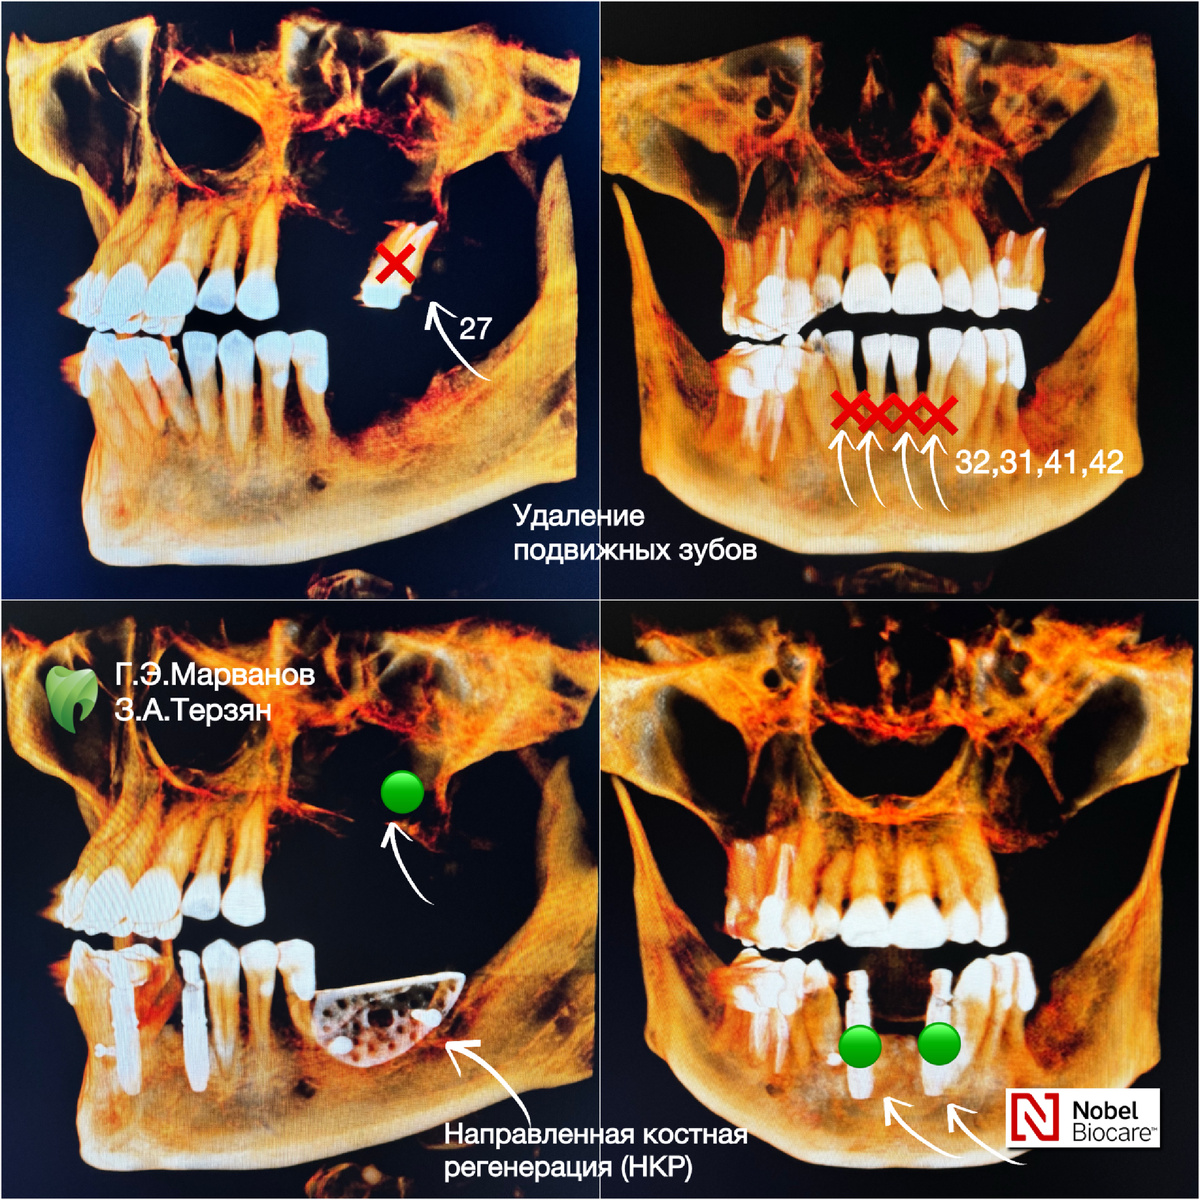

Сегодня кейс с результатами имплантации, включая НКР, - понятное для имплантологов, абсолютно новое для пациентов. Что это? Направленная костная регенерация (НКР) — современный метод восстановления утраченных участков костной ткани, который активно применяется для подготовки к имплантации и в случае утраты зубов по причине пародонтита. Этот процесс обеспечивает полноценное формирование костной ткани в областях с недостаточным объемом благодаря созданию свободного пространства, где костная ткань постепенно образуется. Теперь, все по порядку… Пациентка 52-х лет, обратилась с жалобами на: -подвижность 41,42,31,32 зубов (центральные резцы снизу) и зуба 27; -отсутствие некоторых зубов снизу и сверху слева. Данное лечение мы провели в два этапа: 1-дентальная одномоментная имплантация NobelActive (Швеция) фронтальной группы зубов нижней челюсти с костной и десневой пластикой: 31,32,41,42 и 27 зубов. Т.е. мы удалили подвижные зубы и сразу установили имплантаты по навигационному шаблону. В этот

Направленная костная регенерация (НКР) — современный метод восстановления утраченных участков костной ткани, который активно применяется для подготовки к имплантации и в случае утраты зубов по причине пародонтита. Этот процесс обеспечивает полноценное формирование костной ткани в областях с недостаточным объемом благодаря созданию свободного пространства, где костная ткань постепенно образуется.

-подвижность 41,42,31,32 зубов (центральные резцы снизу) и зуба 27;

-отсутствие некоторых зубов снизу и сверху слева.

1-дентальная одномоментная имплантация NobelActive (Швеция) фронтальной группы зубов нижней челюсти с костной и десневой пластикой: 31,32,41,42 и 27 зубов.

Т.е. мы удалили подвижные зубы и сразу установили имплантаты по навигационному шаблону.

В этот же день врач стоматолог-ортопед, запротезировал этот сегмент челюсти и пациентка ушла домой с передними зубами.

2-направленная костная реабилитация (НКР) - восстановление кости 3-го сегмента на нижней челюсти с помощью титановой мембраны. На фото мы измерили ширину гребня гребня до НКР и после.

Врачам удалось увеличить ширину гребня на 6 мм

Г.Э. Марванов - врач стоматолог-хирург-имплантолог,

З.А. Терзян - врач стоматолог-ортопед.